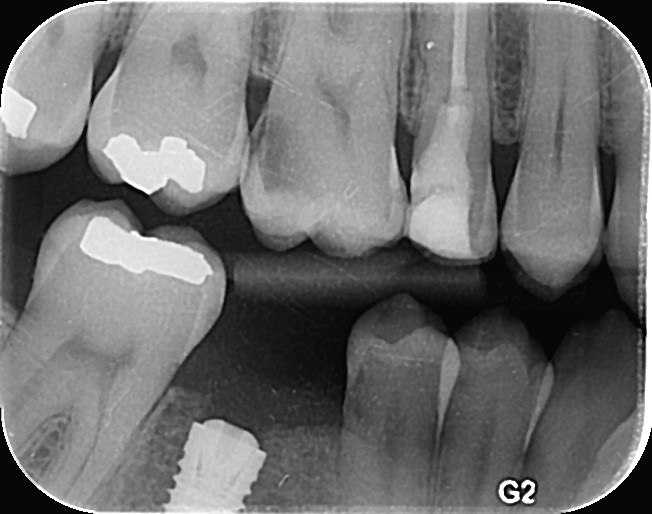

3. What is the caries level on the distal surface of the tooth # 3.6?

6: What is the caries level of mesial of the tooth # 3.6?

7: What is the caries level of Distal of the tooth # 3.6?

11. What is the caries level of the distal surface of the toot # 3.5?

16. What are the caries level in mesial and distal surfaces of the tooth # 4.6 respectively?

17. What is the Caries level on distal surface of the tooth # 3.5?

19. What are the caries level in mesial surface of tooth # 3.8 and distal surface of tooth # 3.7 respectively?

36. What is the caries level of the distal surface of the tooth # 3.4 and mesial surface of the tooth # 3.5 respectively?

37. What is the caries level of distal of the tooth # 3.6?

39. What are the caries level in distal surface of the tooth # 3.4 and mesial surface of the tooth # 3.5?